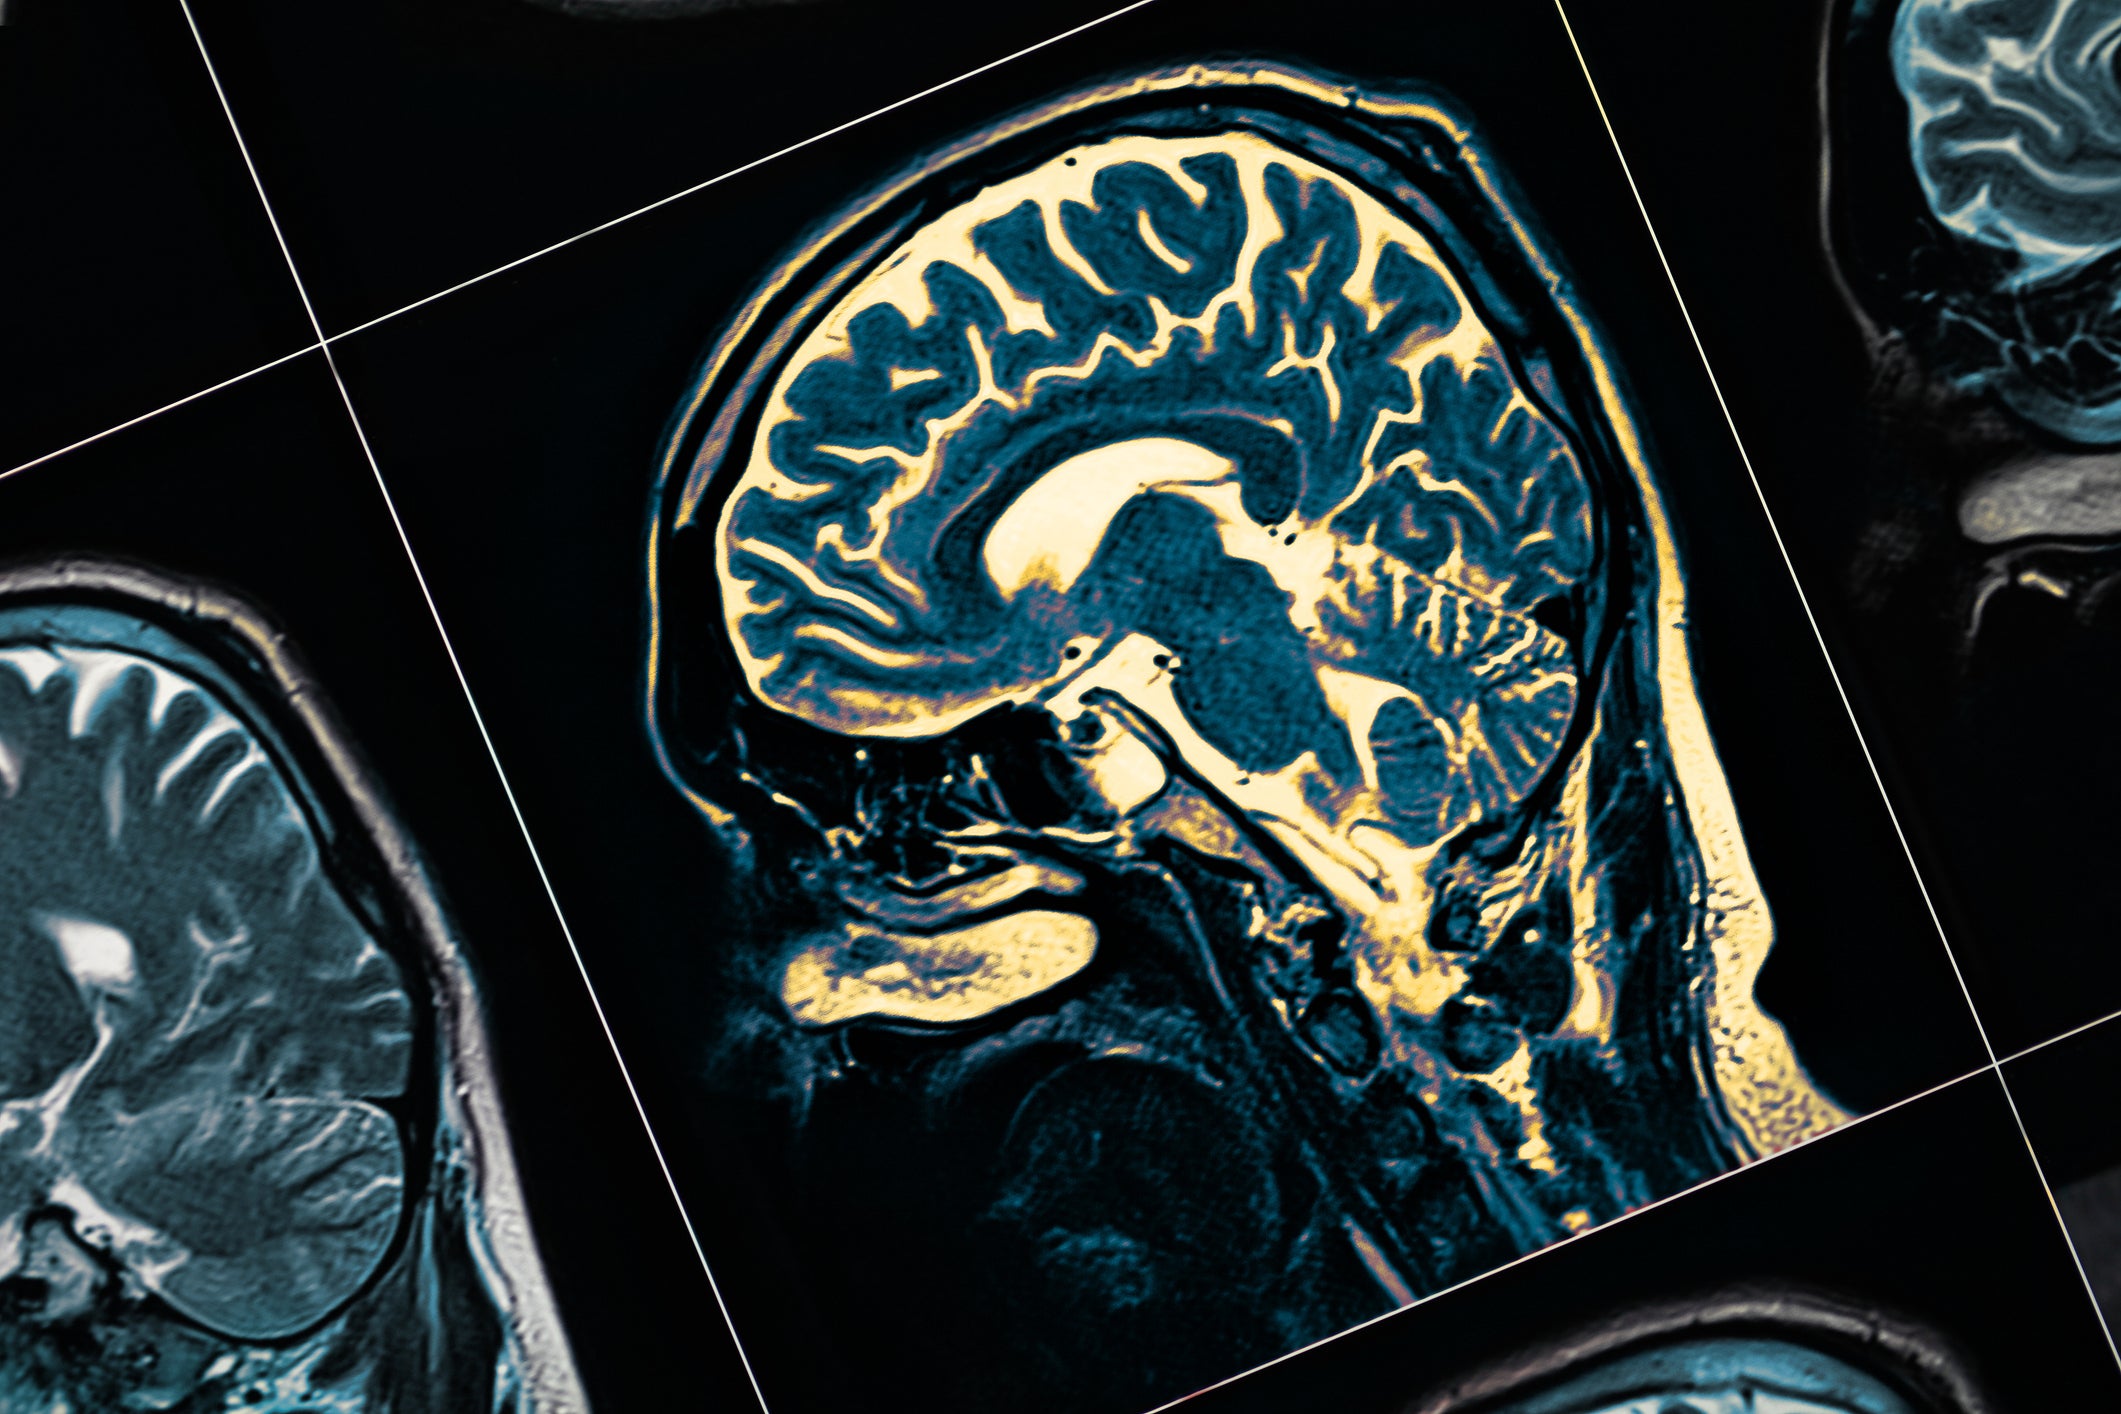

Scientists have developed a groundbreaking technique enabling them to visualise tiny brain clusters believed to trigger Parkinson’s disease.

Researchers hailed the breakthrough, likening it to “being able to see stars in broad daylight”. This discovery is hoped to deepen understanding of Parkinson’s development, potentially paving the way for new treatments.

A hallmark of the disease is the presence of abnormal protein clumps, known as Lewy bodies, in the brain.

However, some researchers suggest these form from smaller clusters known as alpha-synuclein oligomers – which are small, toxic clumps of a protein called α-synuclein.

This idea is “controversial”, according to experts at the University of Cambridge, UCL, the Francis Crick Institute and Polytechnique Montréal, as it has not been possible to directly visualise these clusters in human brain tissue until now.

The team has developed a technique called Advanced Sensing of Aggregates for Parkinson’s Disease – or ASA-PD – which uses ultra-sensitive fluorescence microscopy.

The process involves scientists attaching fluorescent dyes to specific molecules or structures inside human brain cells.

When the microscope shines a laser on these dyes, it causes the structures to glow, letting experts see very dim signals.

As protein oligomers are so tiny, their signal is very weak, and ASA-PD maximises the signal while decreasing the background.

For the study, researchers examined post-mortem brain tissue samples from people with Parkinson’s and compared them to healthy individuals of similar age.

They found that oligomers existed in all samples, but they were larger and brighter in disease samples.

The team also discovered a sub-class of oligomers unique to Parkinson’s patients.